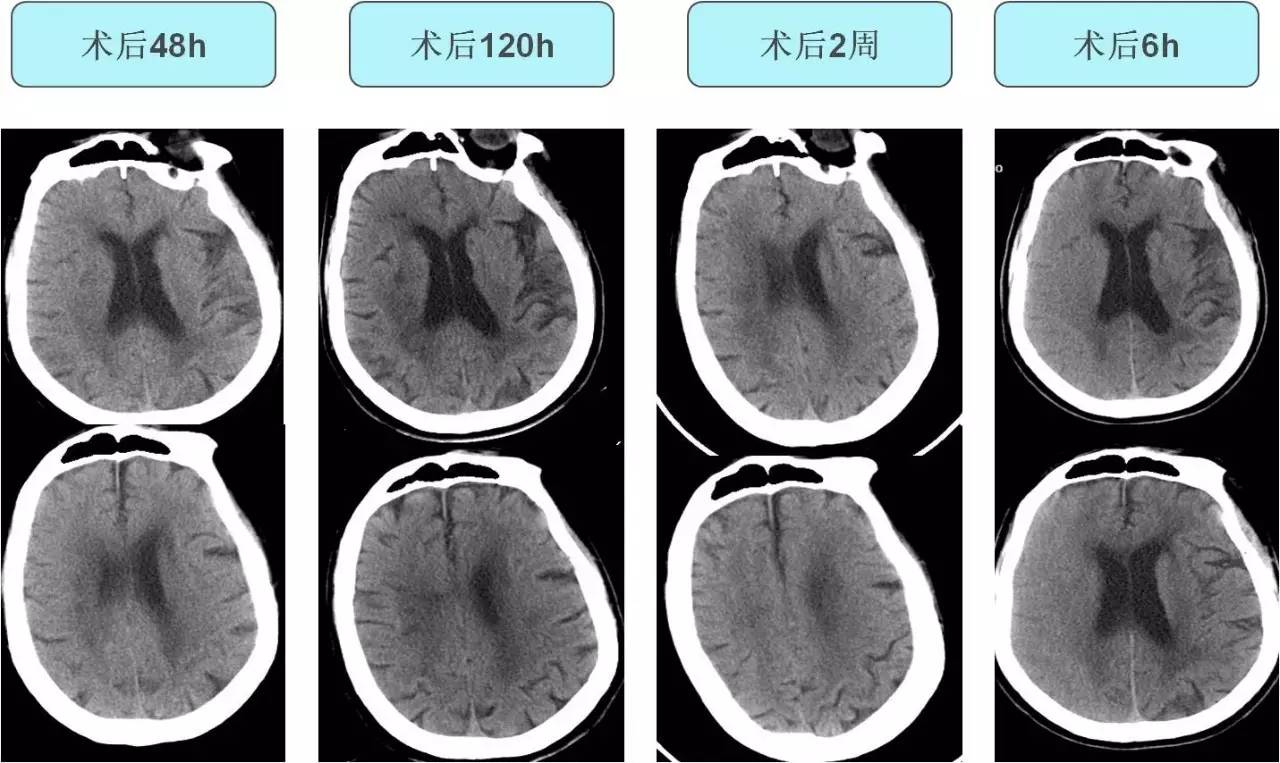

不同时间CT表现

#头颅CT:传统头部CT通常对于早期识别CHS帮助很小,头部CT提示弥漫性或片状白质水肿、占位效应或术侧颅内出血可能与CHS有关。

#头颅MR:CHS在MRI上的异常表现包括白质水肿、局灶性梗死、局限性或大范围出血等,同时MRA可以对颅内外的血管进行无创评估。但CAS术后目前头颅MR检查相对禁忌。